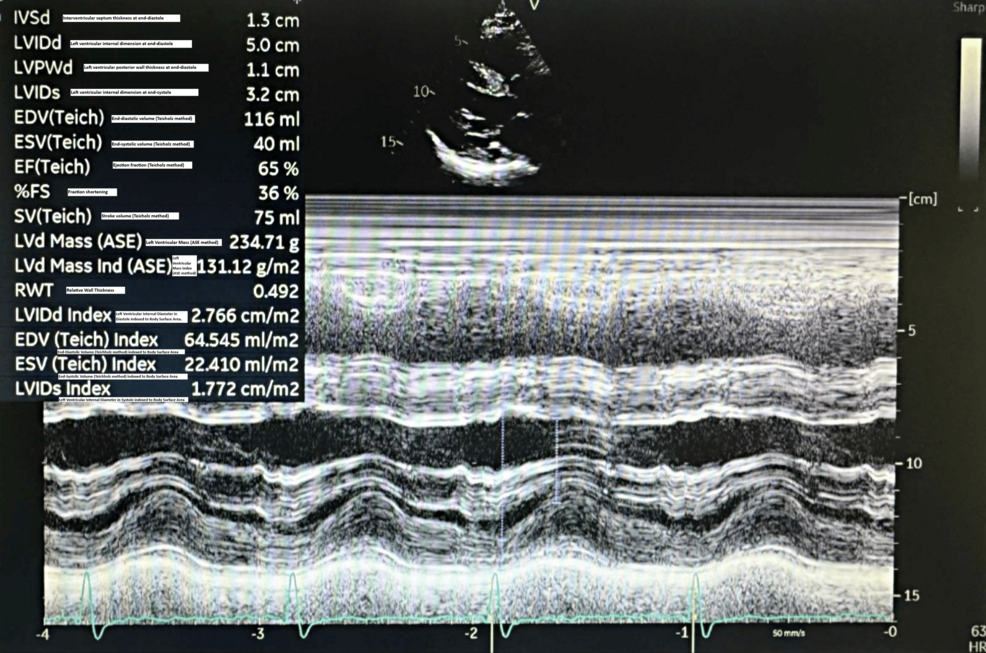

An 80-year-old male presented to the Emergency Department following a fall resulting in a closed left femoral neck fracture. He was scheduled for closed reduction and internal fixation with a trochanteric femoral nail advanced (TFNA) as confirmed by X-ray pelvis showing a “mildly displaced intertrochanteric fracture of left femur” (Figure 1). His medical history included coronary artery disease with prior coronary stenting (echocardiography revealed preserved systolic function (ejection fraction 55-60%), Grade I diastolic dysfunction, and no valvular lesions, regional wall motion abnormalities, or pulmonary hypertension, indicating low perioperative risk for anesthesia), poorly controlled hypertension, end-stage renal disease requiring twice-weekly hemodialysis, and well-controlled type 2 diabetes mellitus. Additional conditions included benign prostatic hyperplasia, bilateral renal cortical cysts, and cystitis. His medications comprised bisoprolol, aspirin, enoxaparin (substituted for clopidogrel preoperatively), insulin, ezetimibe, and topical beta-sitosterol, with no reported drug allergies.

Preoperative evaluation classified the patient as American Society of Anesthesiologists (ASA) physical status 3, reflecting severe systemic disease. The Revised Cardiac Risk Index (RCRI) score indicated Class III, with a major adverse cardiac event risk exceeding 10.1% [4]. Electrocardiography showed sinus rhythm with right bundle branch block (Figure 2), while chest radiography was unremarkable. Airway assessment revealed a Mallampati Class II score, full cervical mobility, and removable partial dentures. Laboratory findings (Table 1) included elevated serum creatinine (4.98 mg/dL), mild hyperkalemia (5.7 mmol/L), mild anemia (hemoglobin of 11.6 g/dL), and a normal international normalized ratio (INR: 1.00). Imaging confirmed the femoral neck fracture, with ultrasonography noting renal cysts (Figure 3) and prostatic enlargement (Figure 4). An echocardiogram was normal (Figure 5). Cardiology consultation advised continuing bisoprolol, resuming aspirin postoperatively, and bridging anticoagulation with enoxaparin, discontinued 24 hours preoperatively. Recent hemodialysis stabilized electrolytes, optimizing the patient for surgery.